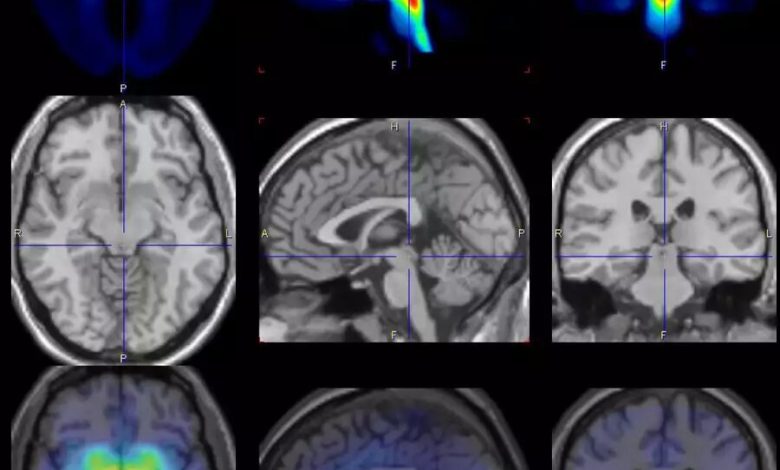

Os cientistas tiraram imagens do cérebro das mulheres com tomografia por emissão de pósitrons (PET) em diferentes tempos de ciclo. Crédito: MPI CBS

“Examinamos 30 pacientes do sexo feminino e 29 participantes saudáveis do estudo ao longo de vários ciclos menstruais e tiraram imagens do cérebro com tomografia por emissão de pósitrons (PET) em diferentes tempos de ciclo. Descobrimos que pouco antes do início da menstruação, o transportador de serotonina no cérebro está aumentado e, portanto, promove uma perda sináptica desse neurotransmissor, o que pode explicar os sintomas afetivos nas mulheres afetadas.